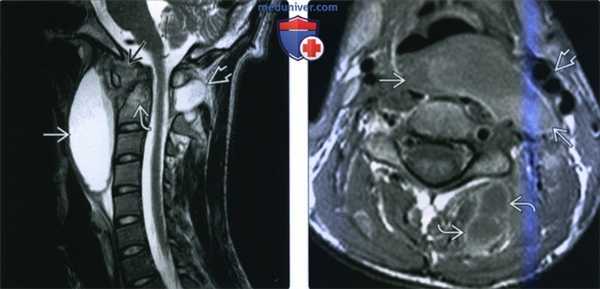

(Слева) Фронтальный срез, STIR МР-И: в толще отечной левой поясничной мышцы видны множественные гиперинтенсивные жид костные скопления. Эти паравертебральные абсцессы скорее всего гематогенного происхождения (пациент являлся внутривенным наркоманом). STIR-режим наиболее информативен в отношении раннего выявления паравертебральных очагов воспаления.

(Справа) Аксиальный срез, Т1-ВИ, FS с КУ: множественные небольшие контрастирующиеся по периферии и гипоинтенсивные в центре жидкостные образования в толще обеих поясничных мышц. Поверхностные абсцессы были дренированы чрескожно со стороны спины.

(Слева) МРТ Т1ВИ с КУ, аксиальная проекция. Однородное накопление контраста в предпозвоночных мышцах с увеличением их объема. Жировая клетчатка заглоточного пространства смещена кпереди. Имеются признаки аномального накопления контраста в эпидуральном пространстве, происходит формирование эпидурального абсцесса, окруженного кольцом накопления контраста.

(Справа) MPT STIR в сагиттальной проекции у пациента со спондилодисцитом С6-С7 позвонков. Отмечается сужение межпозвоночного пространства, аномально гиперинтенсивный сигнал от тел позвонков. Имеются признаки предпозвоноччной флегмоны и эпидурального абсцесса. Имеется выраженное сдавливание спинного мозга.